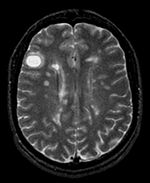

Unregistered baseline data: PD vs. T1Gd Unregistered followup data: PD exam 2 vs. exam 1

Registered baseline data Registered followup data